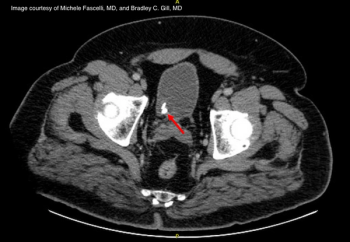

A 61-year-old female complains of acute-onset right-sided flank and abdominal pain. She describes associated nausea, but denied urinary symptoms, hematuria, fever, or chills.